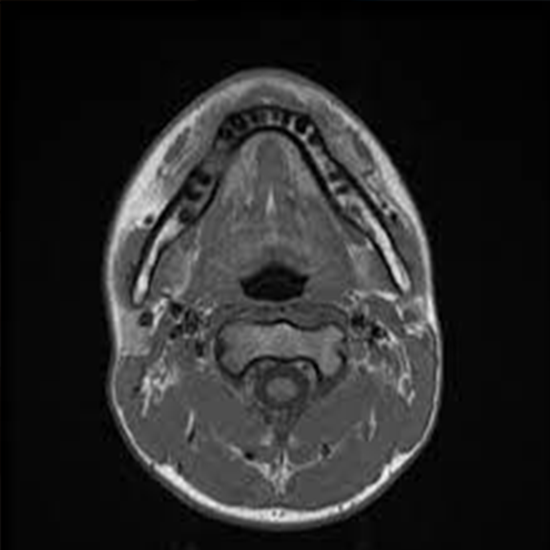

MRI Mandible is an imaging procedure that plays an important role in the imaging pathology of the mandible. It helps in detecting the abnormalities of the mandible, and differentiate between solid and cystic lesions